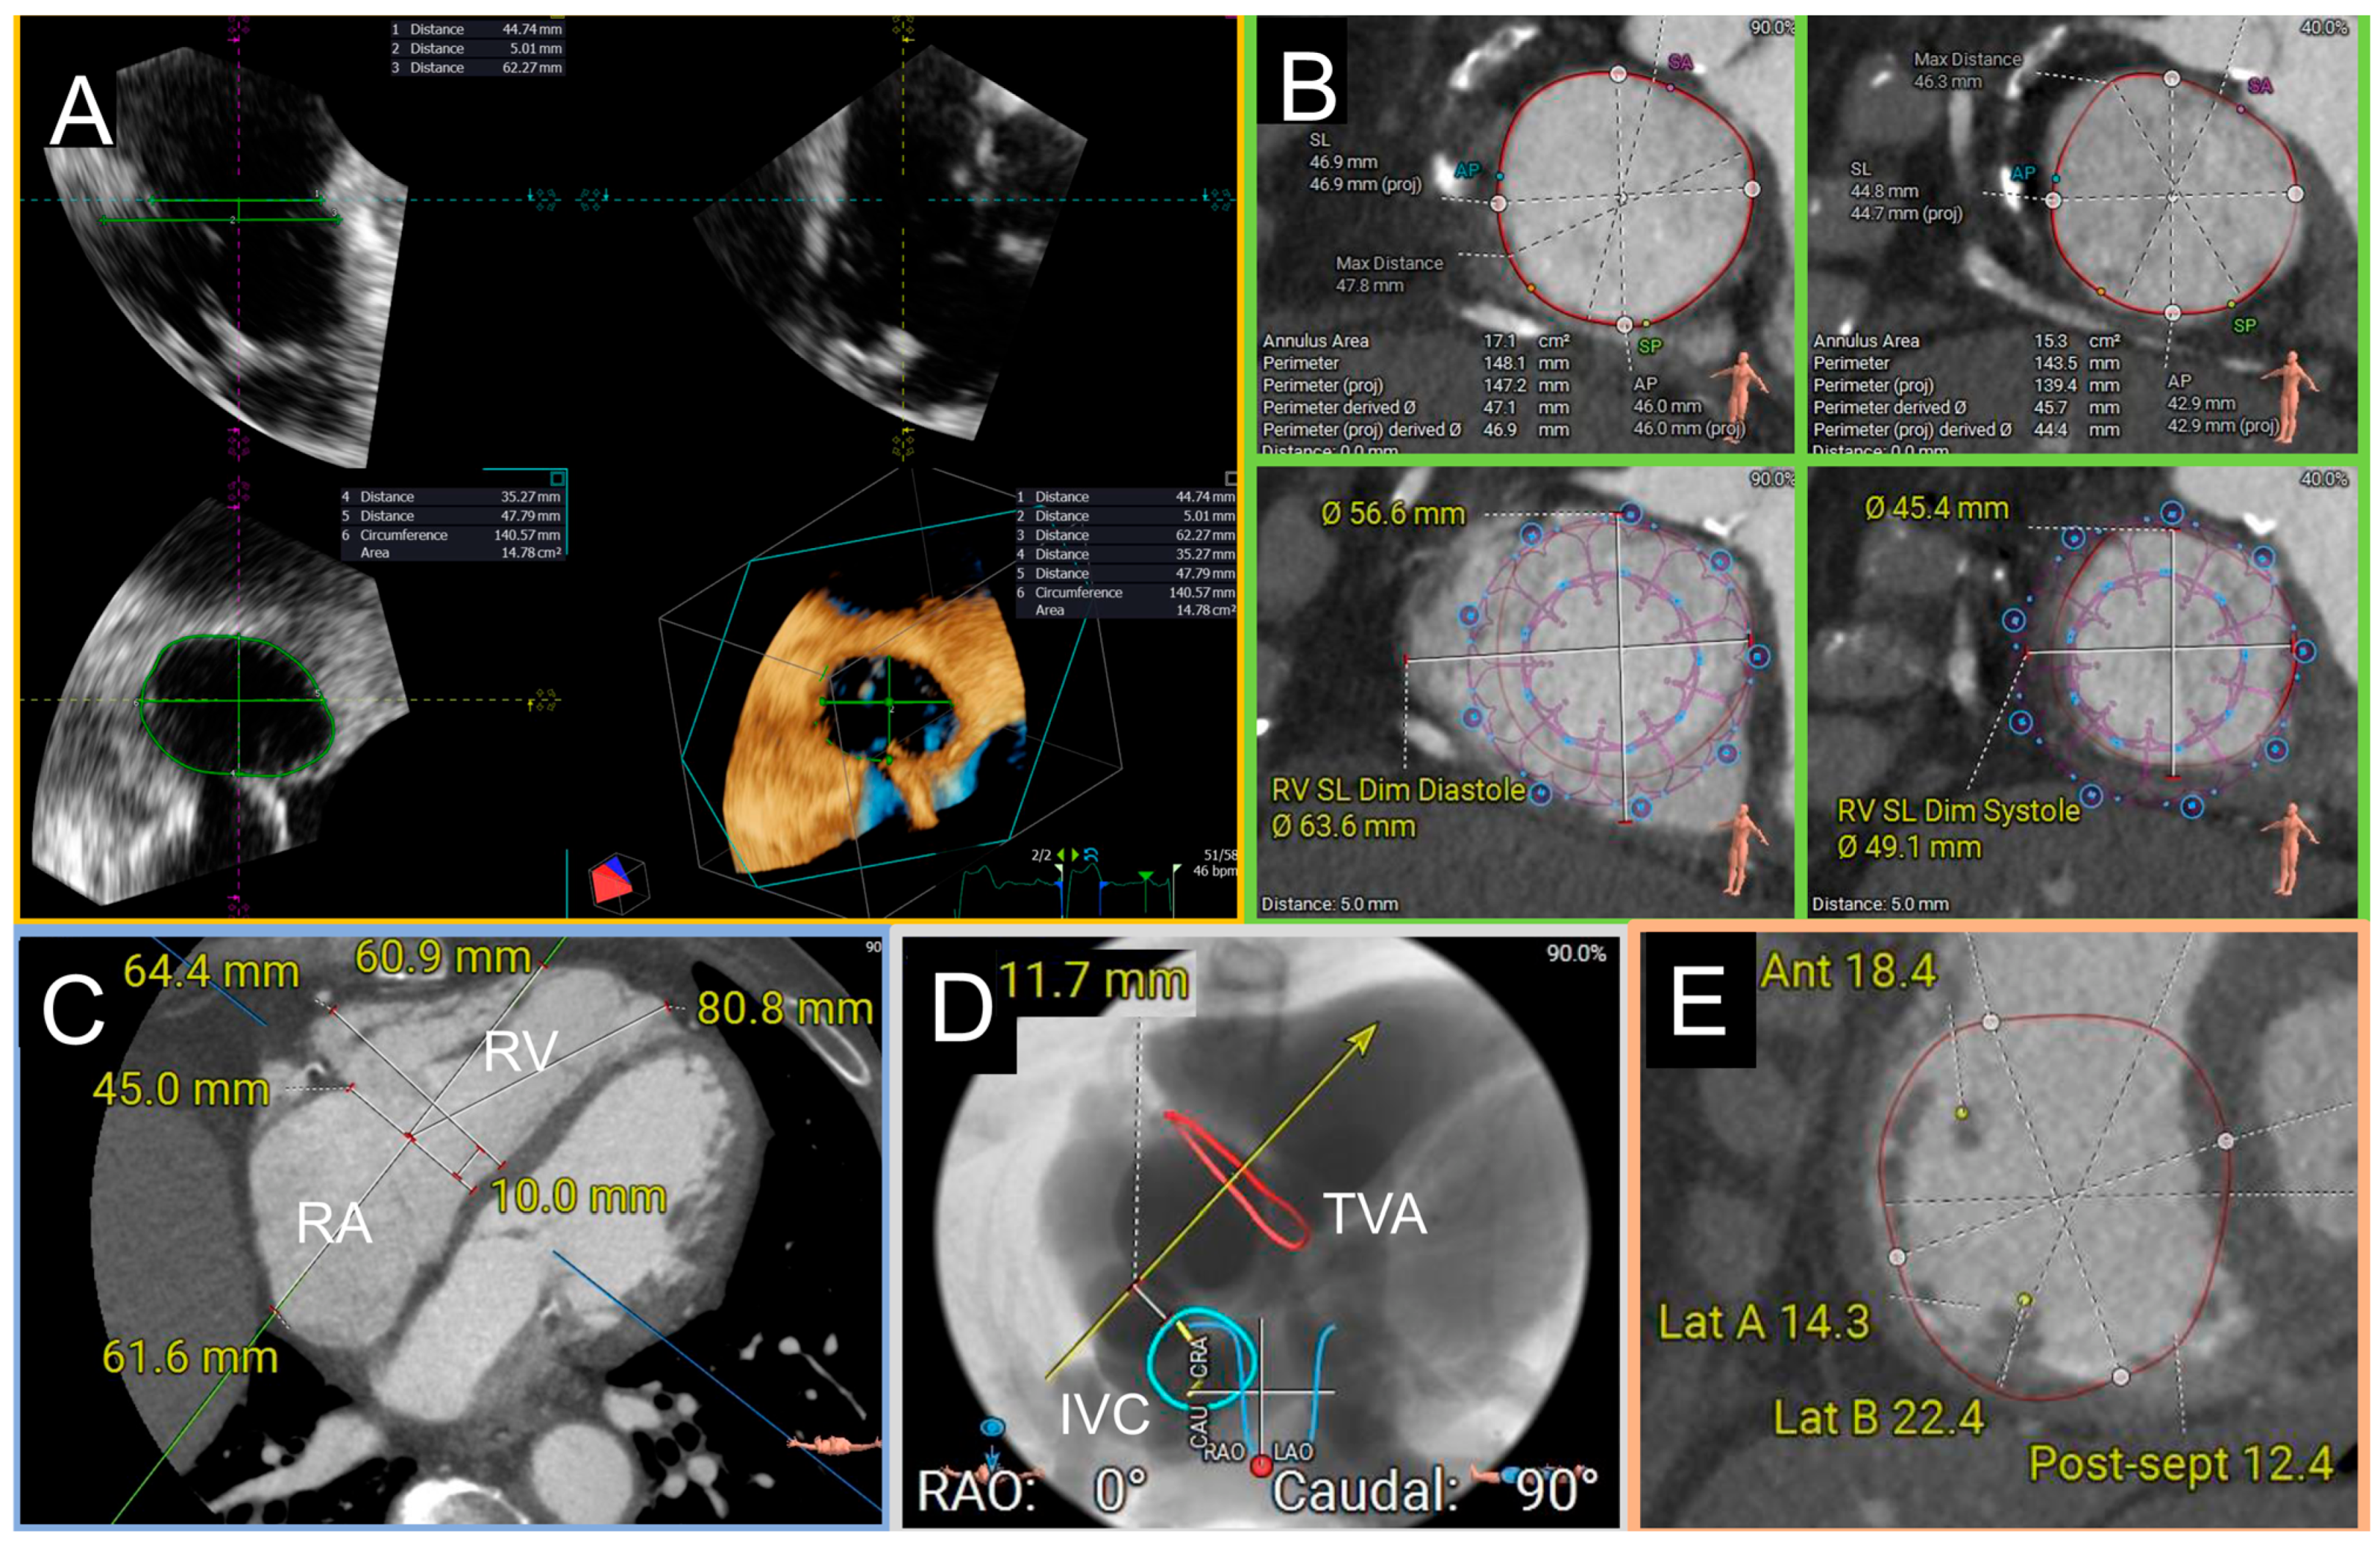

- Annular sizing: the main reason for screening failure is represented by excessive annular dimensions [111]. With TEE, a perimeter > 160 mm or a 2D diameter > 60 mm are considered highly predictive of screening failure at CT due to excessive annular size. The nominal sizes of the Evoque valve are based on the outer frame diameter of the valve; these diameters are compared to annular dimensions calculated at CT using the projected perimeter derived diameter (PDD, Figure 8). Valve sizing is not only based on pure annular dimensions, but also on the degree of annular oversizing. Annular oversizing is expressed as “[(valve size − PDD)/PDD] × 100” and positive oversizing is identified when the valve is bigger than the native annulus. A positive oversizing is needed to ensure adequate valve sealing. The degree of oversizing is also calculated at the ventricular basal level (and in this case the outer dimensions at the anchors level is used) and its presence is considered a useful retention mechanism.

- Right chambers size: RA and RV represent the working room of the TTVR procedure; adequate chamber size is needed to manipulate the system and implant the valve. The anatomical working room is generally assessed using a contrast CT scan in diastolic and systolic phases. Using a reformatted 4 chamber view, RA height from the annulus to atrial roof, RV length from the annulus to the apex and the relationship between IVC and TV annulus are assessed [115]. The delivery system must have enough space to orientate and implant the valve without any interference with the surrounding structures. Additionally, CT scan is used to assess the position and the distance of papillary muscles relatively to the annulus: from one side papillary muscles can interfere with valve positioning if they are too close to the valve; from the other side, they can be considered another retention mechanism, thus they can stabilize the ventricular side of the valve after deployment (Figure 8).